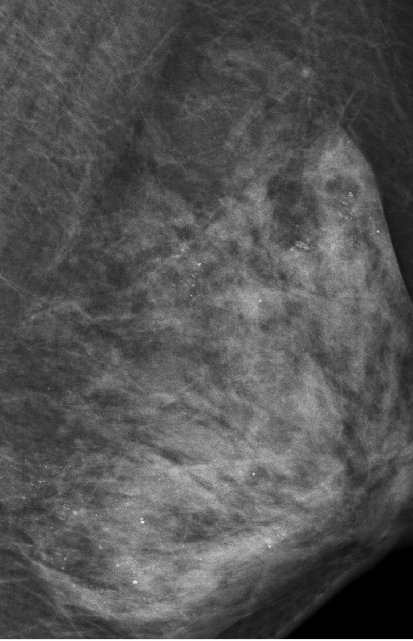

家住江岸区的朱女士,48岁,未婚未育。半年前体检发现右侧乳腺内有一个大小约2厘米包块,近日自觉包块增大,前往武汉市第一医院甲乳外科就诊。右侧乳腺包块最终确诊为乳腺肿浸润性癌,接受了全乳切除加同侧淋巴结清扫。管床医生陶龙介绍,让人意外的是其左侧乳房,乳腺X线检查发现众多细小如沙子一样、呈散在分布的钙化灶,分布广泛,片子上看神似满天星。让医生犯难的是,如此多的细小钙化灶,不知哪些是良性的哪些是恶性!

乳腺沙砾样钙化灶是癌化的信号之一,需高度关注。为进一步确诊,朱女士左侧乳腺做了核磁共振,却并没有发现大的异常,暂时可以排除恶性肿瘤。但其仍处于高度危险状态,只能观察并接受严格复查,每3个月做一次乳腺彩超,如发现可疑病灶,再行手术治疗。

为寻找病因,陶龙医生详询病史,问她是不是做过什么治疗。朱女士告之,自己一向注重保养,常年在外接受精油推拿按摩保养胸部。陶龙推测,极有可能是用力不当损伤了腺叶乳管,导致坏死性细小点状钙化。这种细小点状钙化,极易和癌症沙砾样钙化造成混淆,影响癌症的早期确诊,为进一步明确诊断增加困难,同时严重增加了患者心理负担。